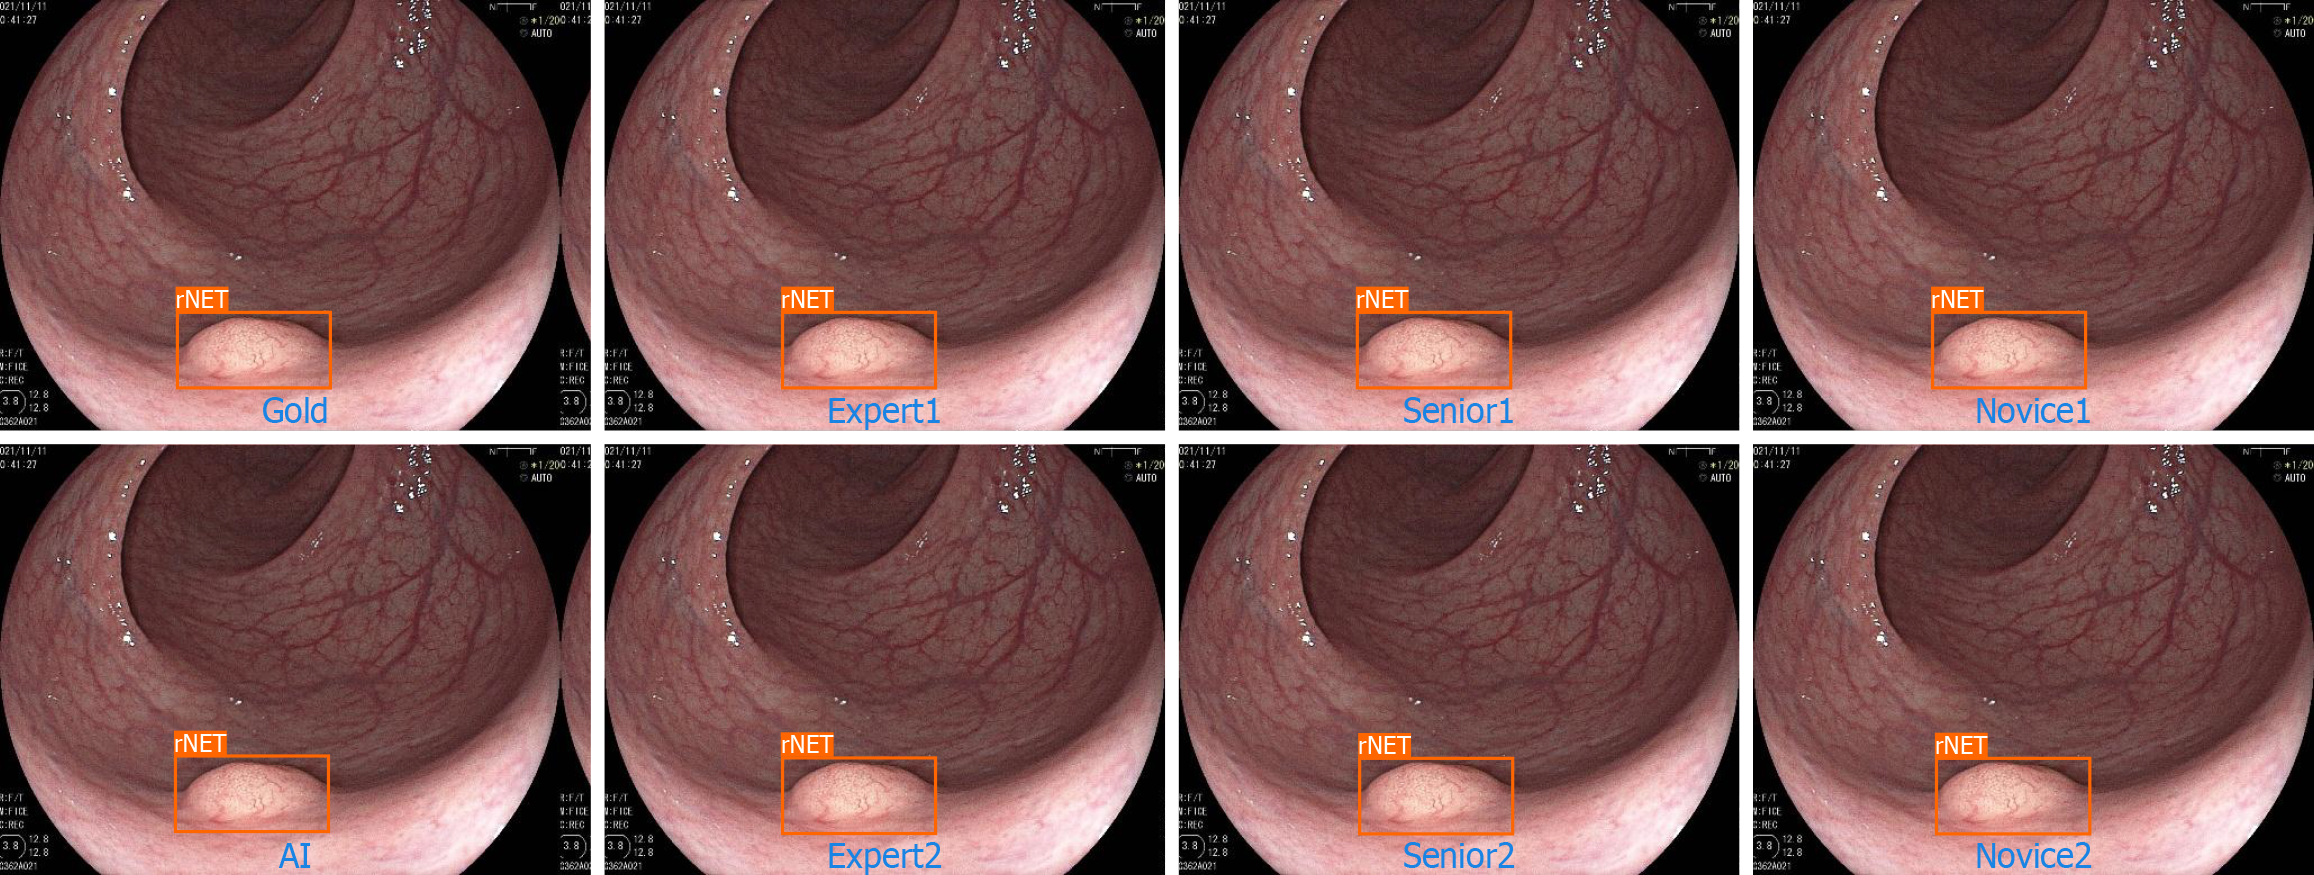

Figure 3 Total right.

rNET: Rectal neuroendocrine tumor.